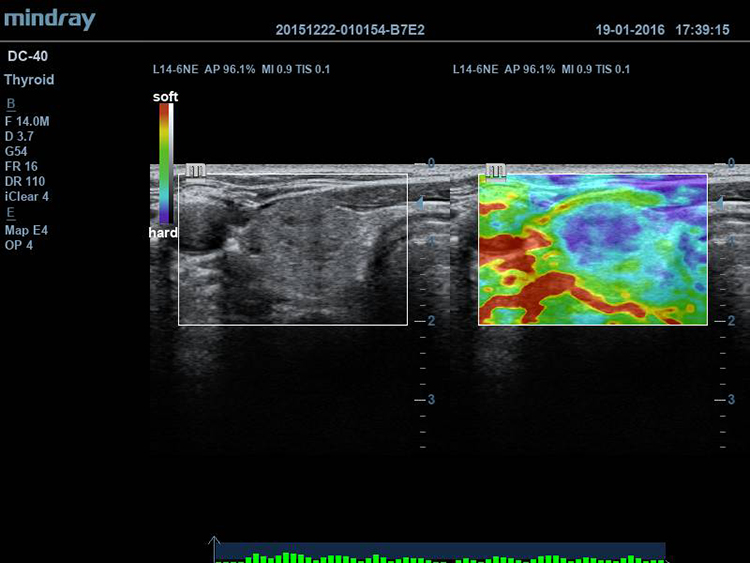

Эластография Natural Touch

Новая технология естественного касания запатентованна Mindray и призвана исключить человеческий фактор, тем самым повышая точность исследований.